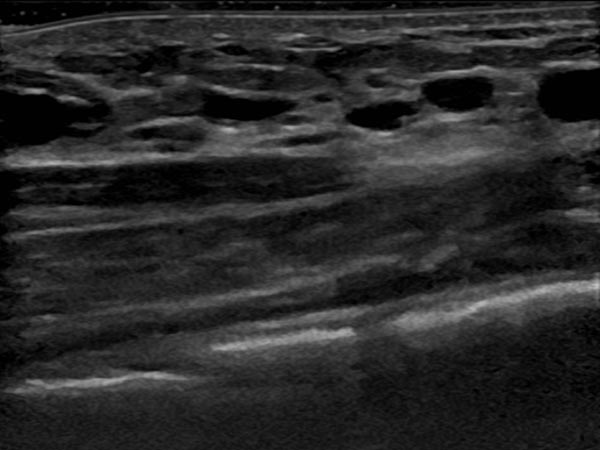

Circumscribed macrocystic malformation on the abdominal wall on ultrasound. Note the anechoic fluid in the thin-walled cystic spaces filled with liquid (lymph).

Ultrasound of the abdominal wall, a little further caudally. Here, the cystic parts of the lymphatic malformation are smaller. However, the lesion is still extraperitoneal in the abdominal wall.